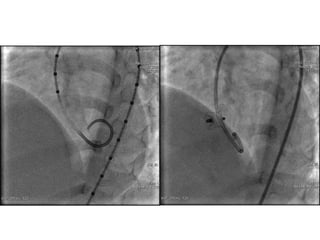

Perimembranous VSD

